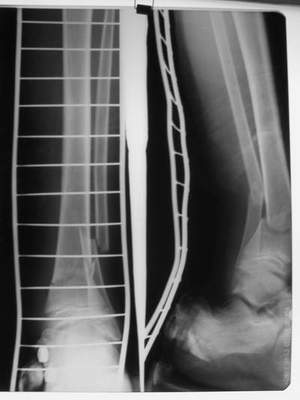

A>> Скелетное вытяжение за пяточную кость.

Так как речь зашла непосредственно о травме, см этапные

снимки. Как все было

Вытяжение